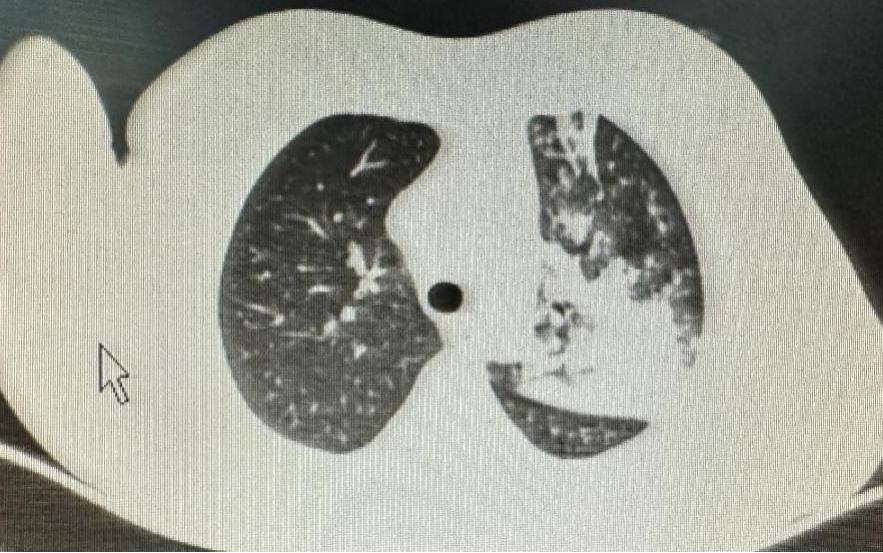

7岁女童,因“发热、咳嗽10天,加重2天”入院。院前曾予治疗,体温无明显好转,入院后治疗3天,体温稍好转,但咳嗽还在持续加重,复查肺部CT提示肺部炎症依旧控制不理想。

反复或持续的高热,咳嗽或不伴有咳嗽,肺部CT都显示出部分肺叶实变,这种波及各年龄段的大叶性肺炎,已引起我科门诊及住院部医生的特别注意。